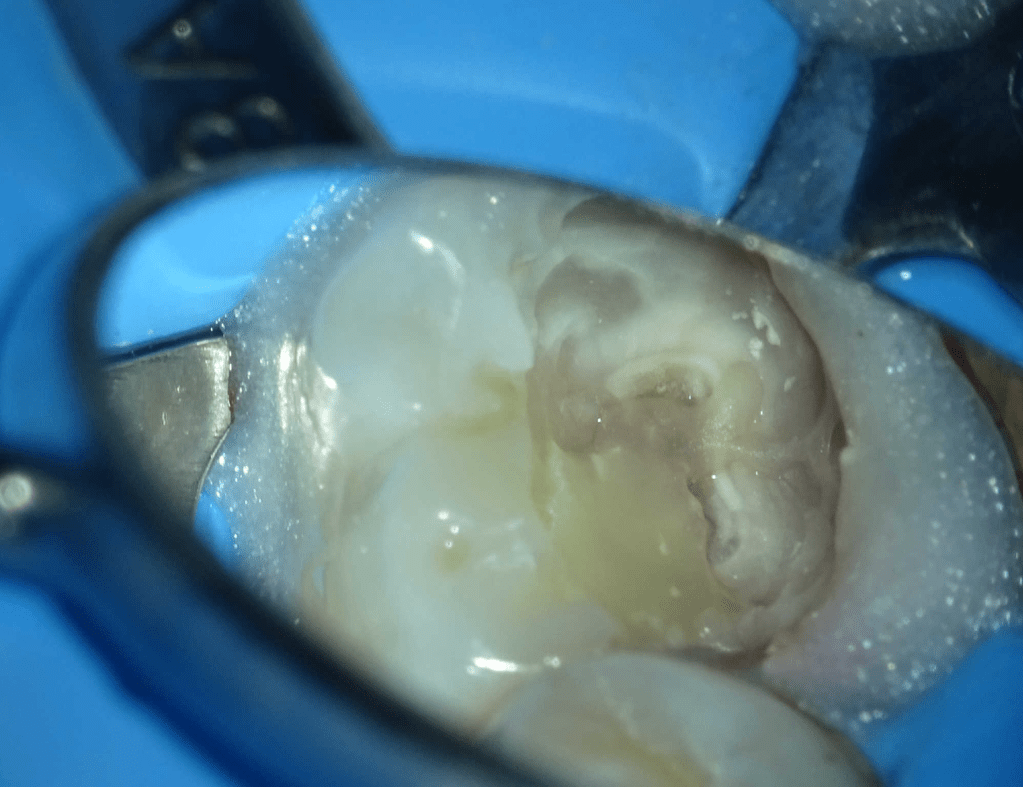

Reco preendo, 2o Molar superior